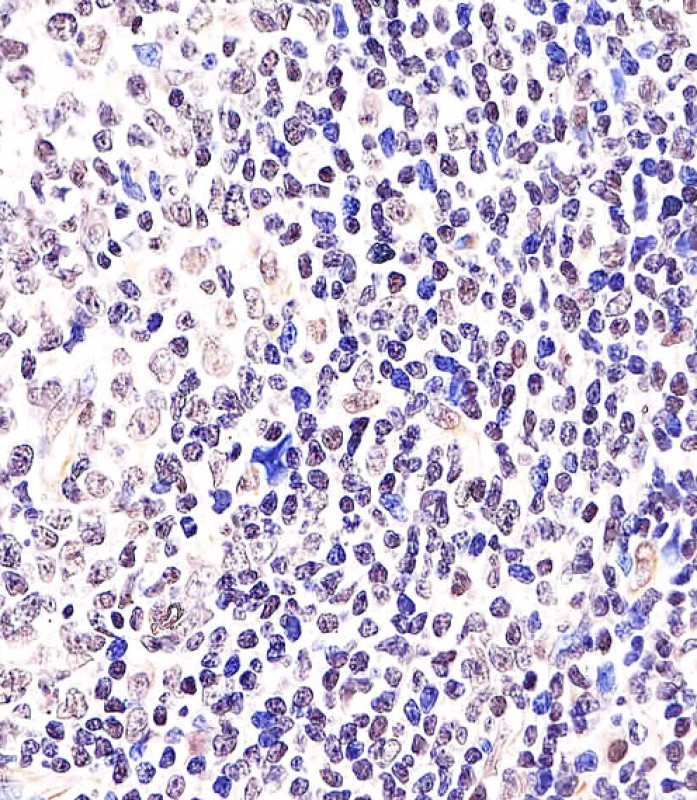

APR04907G staining BCL6 in Human tonsil tissue sections by Immunohistochemistry (IHC-P - paraformaldehyde-fixed, paraffin-embedded sections). Tissue was fixed with formaldehyde and blocked with 3% BSA for 0. 5 hour at room temperature; antigen retrieval was by heat mediation with a citrate buffer (pH6). Samples were incubated with primary antibody (1/25) for 1 hours at 37°C. A undiluted biotinylated goat polyvalent antibody was used as the secondary antibody.